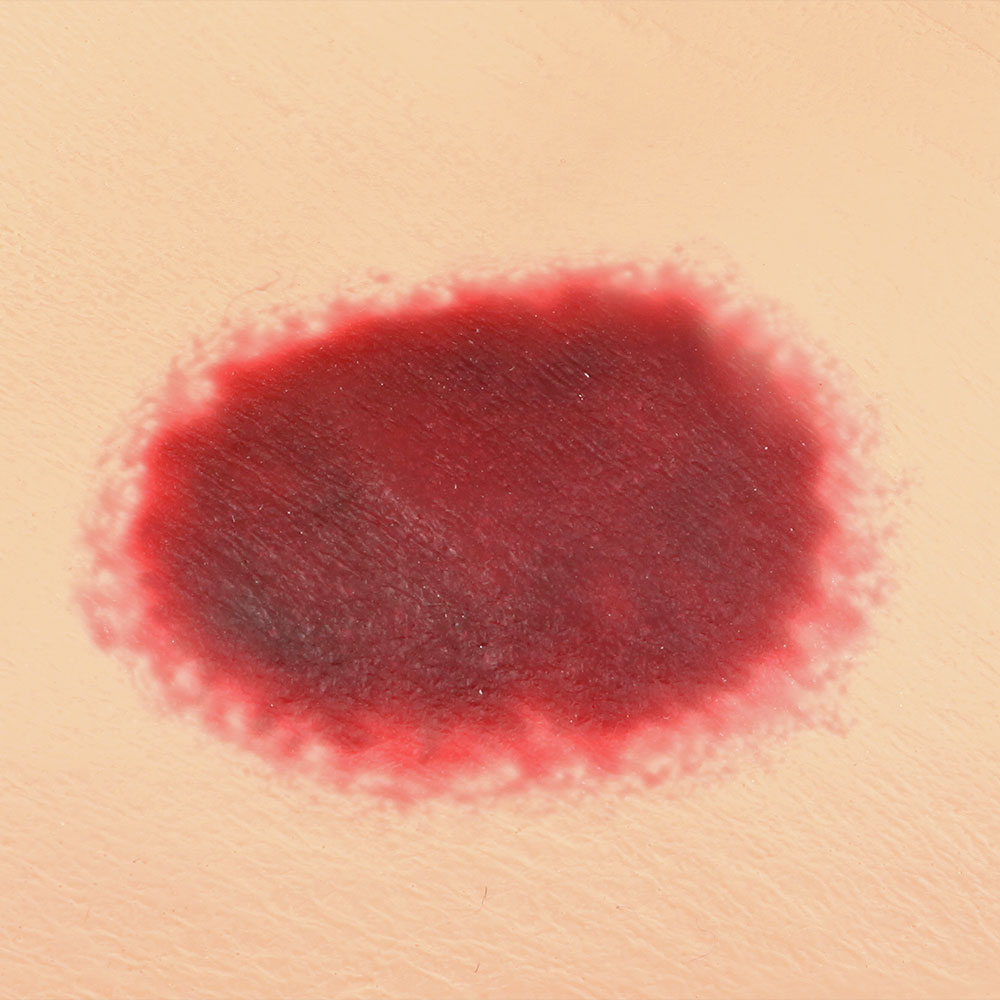

The Seymour II™ Wound Care Model is a highly realistic pressure injury simulator moulded from a 74-year-old patient. It accurately replicates the look and feel of human tissue and presents a wide range of pressure injuries, including Stages 1–4, DTPI, unstageable wounds, and a dehisced wound for advanced wound care training.

- Great care has been taken to hand paint each wound just as you would see it on a patient for the most life-like patient training scenario

- The Seymour patient simulation model makes it possible to visualize and understand the differences in wounds

- Wound care simulation model displays the following pressure injuries:

- DTPI (Deep Tissue Pressure Injury)